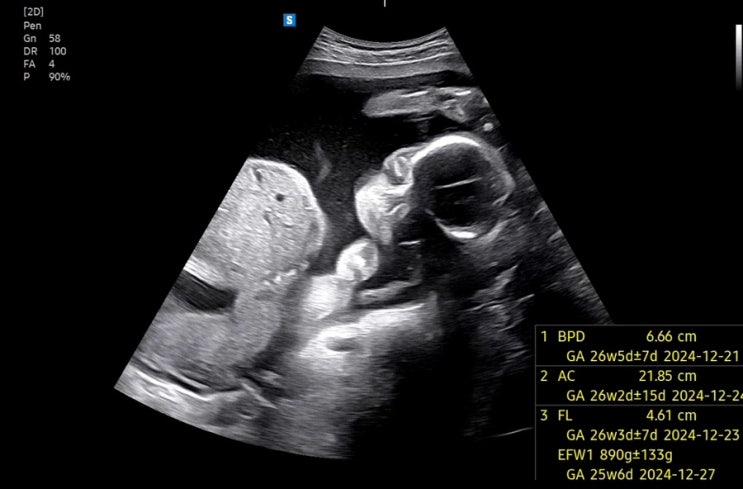

임신 26주차 / 봄빛병원 임당 재검 통과

9/23 임당재검 전 날 저녁으로 프레쉬(?)하게 포케를 먹었는데 소스는 안프레쉬함 9/24 임당.. 147 나와서 ...

임신 25주차 / 두려운 임당검사 그리고 기침하다 허리 나간 임산부